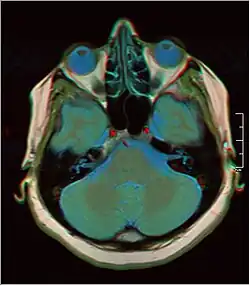

Brain regions on T1 MRI

T1 (note CSF is dark) with contrast (arrow pointing to meningioma of the falx)